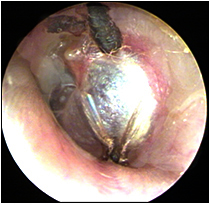

JFC Aticotomía espontánea.